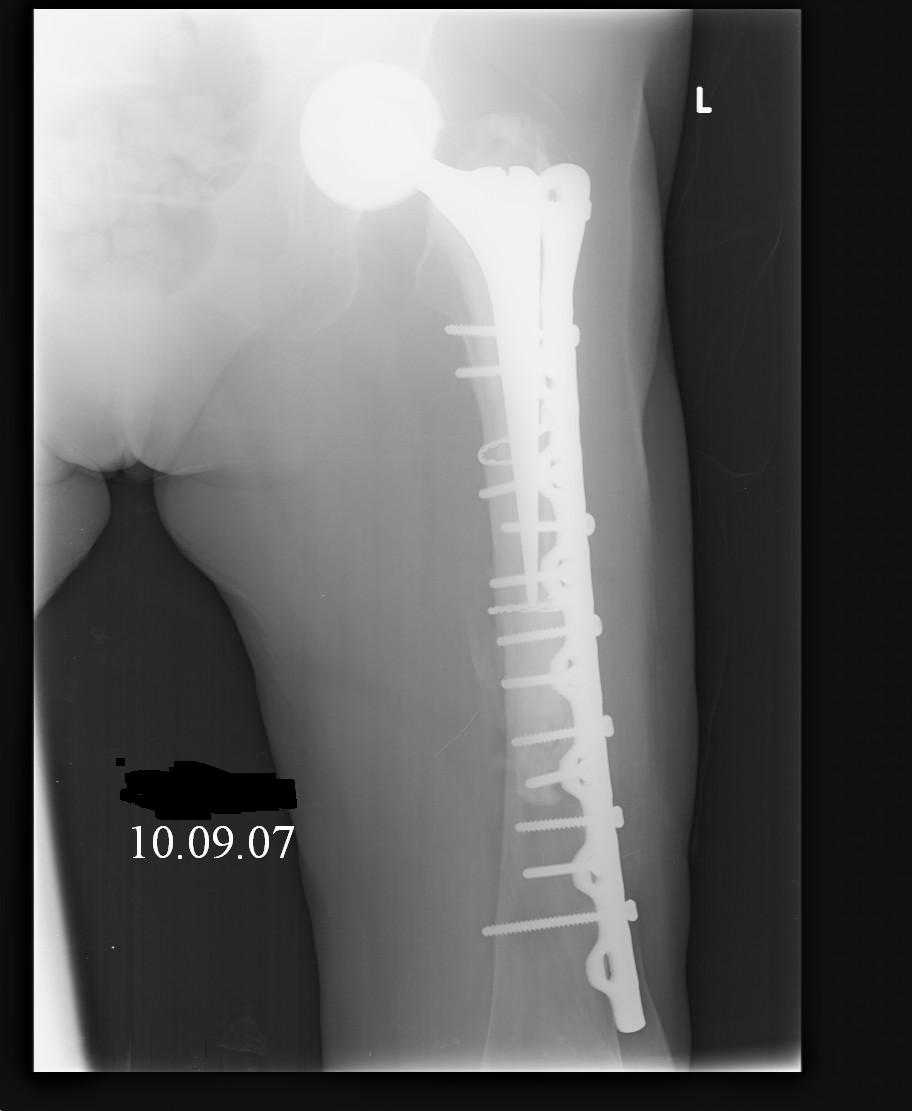

Female, rheumatoid, THA in 2003, car accident in 2006, failed plating. Nailing in Oct 2007. The nail is solid with hollow proximal part where the stem is docked. Last images are in 1 year after

nailing.

Спасибо за обсуждение. После нескольких дней тракции аппаратом сделали. Попытка закрытой репозиции не удалась из-за смещения по ширине, мешали фрагменты цемента. После их удаления репозиция получилась. Еще убрали немного цемента с ножки по латерльной стороне, чтобы обнажить 40-50 мм ее дистальной части, для плотной посадки гвоздя. Дальнейшее введение гвоздя было несложным. Протез показался нам стабильным в проксимальной части как латерально, так и медиально. Картинки в приложении.

THX for the discussion. After few days of traction by ex-fix the surgery was performed. An attempt of closed nailing was unsuccesful because of fragment translation, which was blocked by cement fragments. After removal of broken cement pieces reduction was reached "automagically". Also some cement from lateral part was removed by

chisel to expose distal 40-50 mm of the stem to allow tight fit of the nail. Further fixation by the nail was pretty easy and straightforward. Images attached. The stem looked stable in its proximal part both laterally and medially. Comments/critics are welcome.